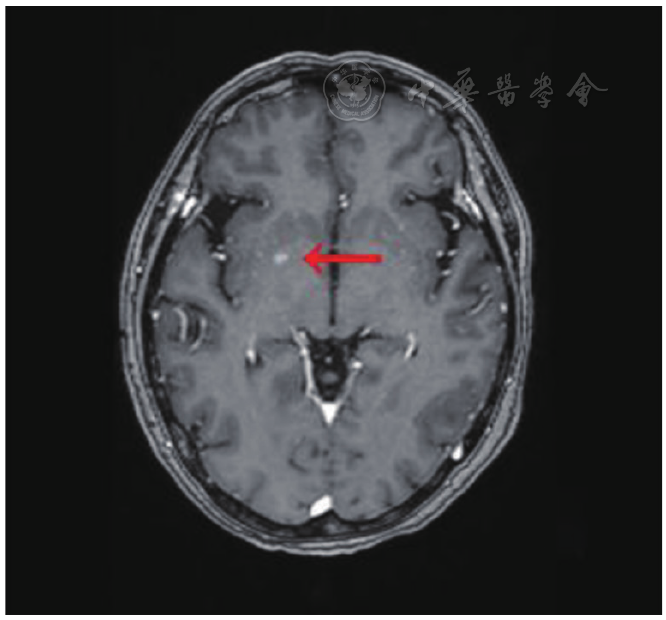

图5 头颅MRI(2022年10月18日)。右侧基底节区强化小结节(红色箭头),提示脑转移。MRI:磁共振